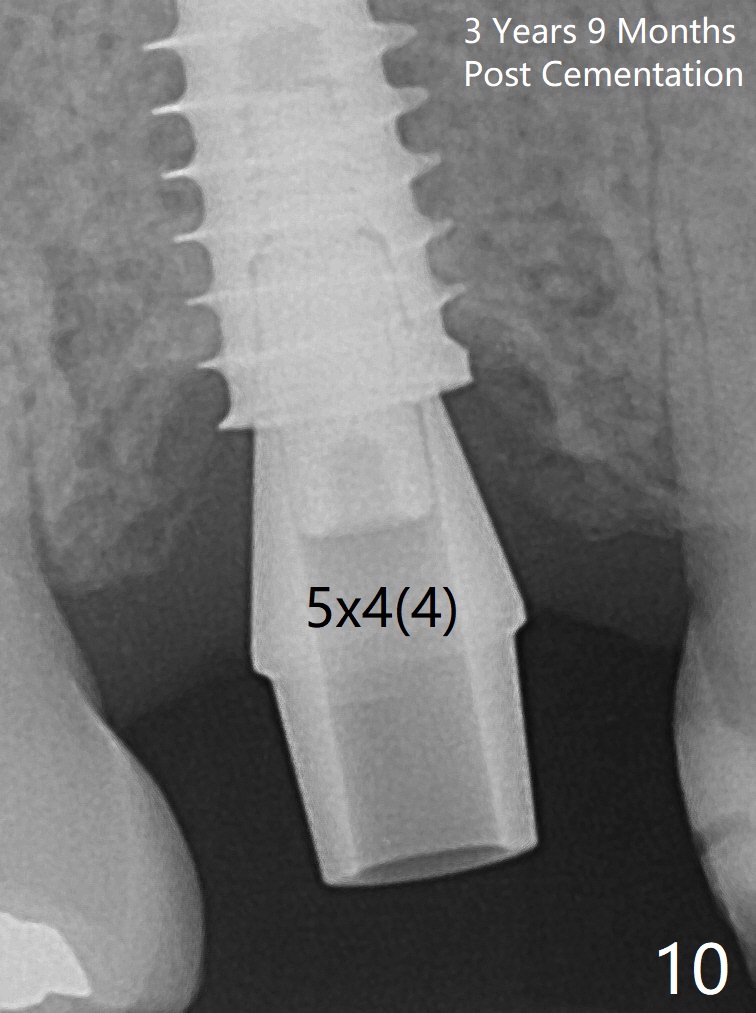

Three weeks postop, the socket has been healing with simultaneous buccal plate collapsing (Fig.5 *, as compared to Fig.2). A larger abutment (7.0-8.5 mm) or a provisional with buccal subgingival margin may decrease the postop shrinking (1,2). There is no bone loss 3 months postop (Fig.6,7). The screw needs to be retightened 9 months post cementation (Fig.8, when the tooth crown is being fabricated at #18). Unilateral mastication is a predisposing factor, since the tooth #19 is missing. When the crown becomes loose again 3 years later, the hex fractures inside the implant. After its removal (Fig.9), a narrower abutment is placed for a new crown (Fig.10: 5x4(4) vs. 6.5x4(4) mm). The implant was placed deep enough without thread exposure; now with apparently complete abutment seating (Fig.11,12). The similar complication may recur due to refusal to have implant at #19 (fear of nerve injury).